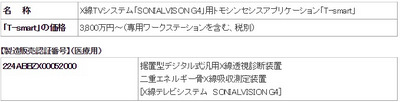

(株)島津製作所は、同社X線TVシステム「SONIALVISION G4」向けに、金属アーチファクト(金属による影のような画像の乱れ)を大幅に低減できる独自のトモシンセシス※1アプリケーション「T-smart」を2015年6月17日に発売するという。

これまで同社は、「T-smart」を、2004年に発売したX線TVシステム「SONIALVISION safire」向けに販売しており、国内外の多数の病院で好評を得ている。今後、より多くの臨床現場でお使いいただくべく、多様な検査やさまざまな検査環境に柔軟に対応できるX線TVシステム「SONIALVISON G4」のオプションとして販売を開始した。